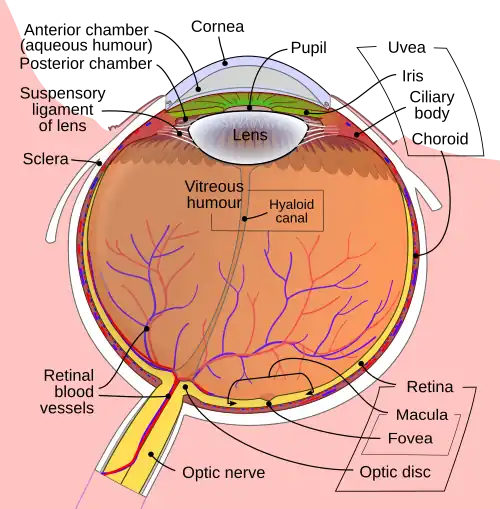

Getting inside of the eyeball - Pupil, iris and the lens

Light rays enter the eye structure through the black aperture or pupil in the front of the eye. The black appearance is due to the light being fully absorbed by the tissue inside the eye. Only through this pupil can light enter into the eye which means the amount of incoming light is effectively determined by the size of the pupil. A pigmented sphincter surrounding the pupil functions as the eye's aperture stop. It is the amount of pigment in this iris, that give rise to the various eye colours found in humans.

In addition to this layer of pigment, the iris has 2 layers of ciliary muscles. A circular muscle called the pupillary sphincter in one layer, that contracts to make the pupil smaller. The other layer has a smooth muscle called the pupillary dilator, which contracts to dilate the pupil. The combination of these muscles can thereby dilate/contract the pupil depending on the requirements or conditions of the person. The ciliary muscles are controlled by ciliary zonules, fibres that also change the shape of the lens and hold it in place.

The lens is situated immediately behind the pupil. Its shape and characteristics reveal a similar purpose to that of camera lenses, but they function in slightly different ways. The shape of the lens is adjusted by the pull of the ciliary zonules, which consequently changes the focal length. Together with the cornea, the lens can change the focus, which makes it a very important structure indeed, however only one third of the total optical power of the eye is due to the lens itself. It is also the eye's main filter. Lens fibres make up most of the material for the lense, which are long and thin cells void of most of the cell machinery to promote transparency. Together with water-soluble proteins called crystallins, they increase the refractive index of the lens. The fibres also play part in the structure and shape of the lens itself.

Beamforming in the eye – Cornea and its protecting agent - Sclera

The cornea, responsible for the remaining 2/3 of the total optical power of the eye, covers the iris, pupil and lens. It focuses the rays that pass through the iris before they pass through the lens. The cornea is only 0.5mm thick and consists of 5 layers:

- Descemet's membrane and Endothelium: Are two layers adjusted to the anterior chamber of the eye filled with aqueous humor fluid produced by the ciliary body. This fluid moisturises the lens, cleans it and maintains the pressure in the eye ball. The chamber, positioned between cornea and iris, contains a trabecular meshwork body through which the fluid is drained out by Schlemm canal, through posterior chamber.

The surface of the cornea lies under two protective membranes, called the sclera and Tenon’s capsule. Both of these protective layers completely envelop the eyeball. The sclera is built from collagen and elastic fibres, which protect the eye from external damages, this layer also gives rise to the white of the eye. It is pierced by nerves and vessels with the largest hole reserved for the optic nerve. Moreover, it is covered by conjunctiva, which is a clear mucous membrane on the surface of the eyeball. This membrane also lines the inside of the eyelid. It works as a lubricant and, together with the lacrimal gland, it produces tears, that lubricate and protect the eye. The remaining protective layer, the eyelid, also functions to spread this lubricant around.

Where the vision reception occurs – The retina

A part of the eye, which marks the transition from non-photosensitive region to photosensitive region, is called the ora serrata. The photosensitive region is referred to as the retina, which is the sensory structure in the back of the eye. The retina consists of multiple layers presented below with millions of photoreceptors called rods and cones, which capture the light rays and convert them into electrical impulses. Transmission of these impulses is nervously initiated by the ganglion cells and conducted through the optic nerve, the single route by which information leaves the eye.